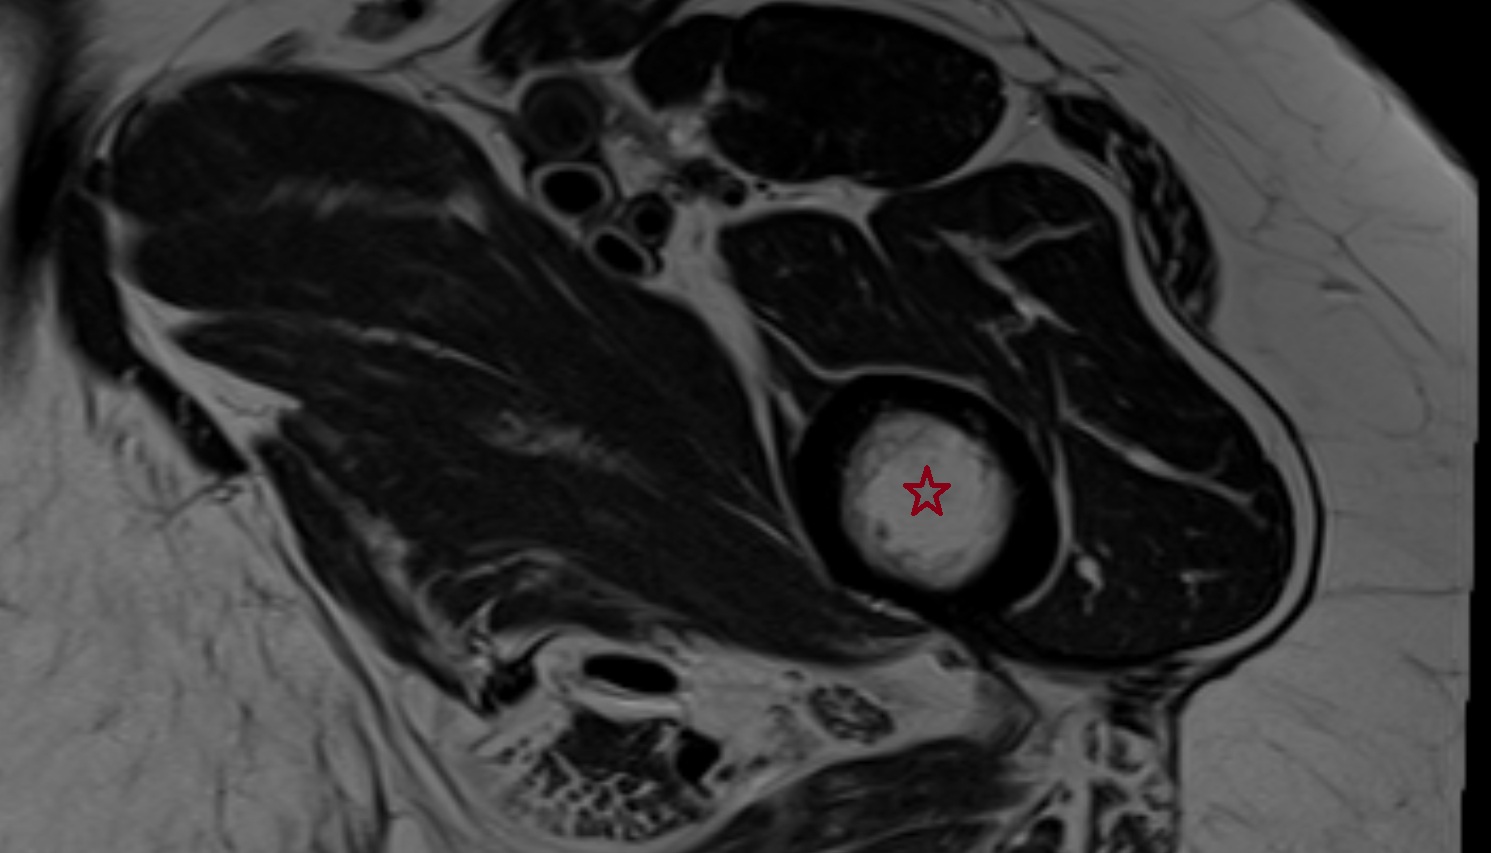

- Peripheral zone of prostate

- Anterior Fibromuscular Stroma of prostate

- Central zone of prostate

- Transitional zone of prostate